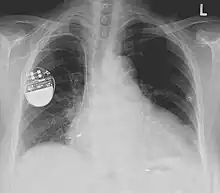

Une radiographie pulmonaire est faite de manière usuelle, après l'intervention, afin de vérifier l'absence de pneumothorax (accident possible en cas de ponction de la veine sous-clavière) et le positionnement des sondes[14].